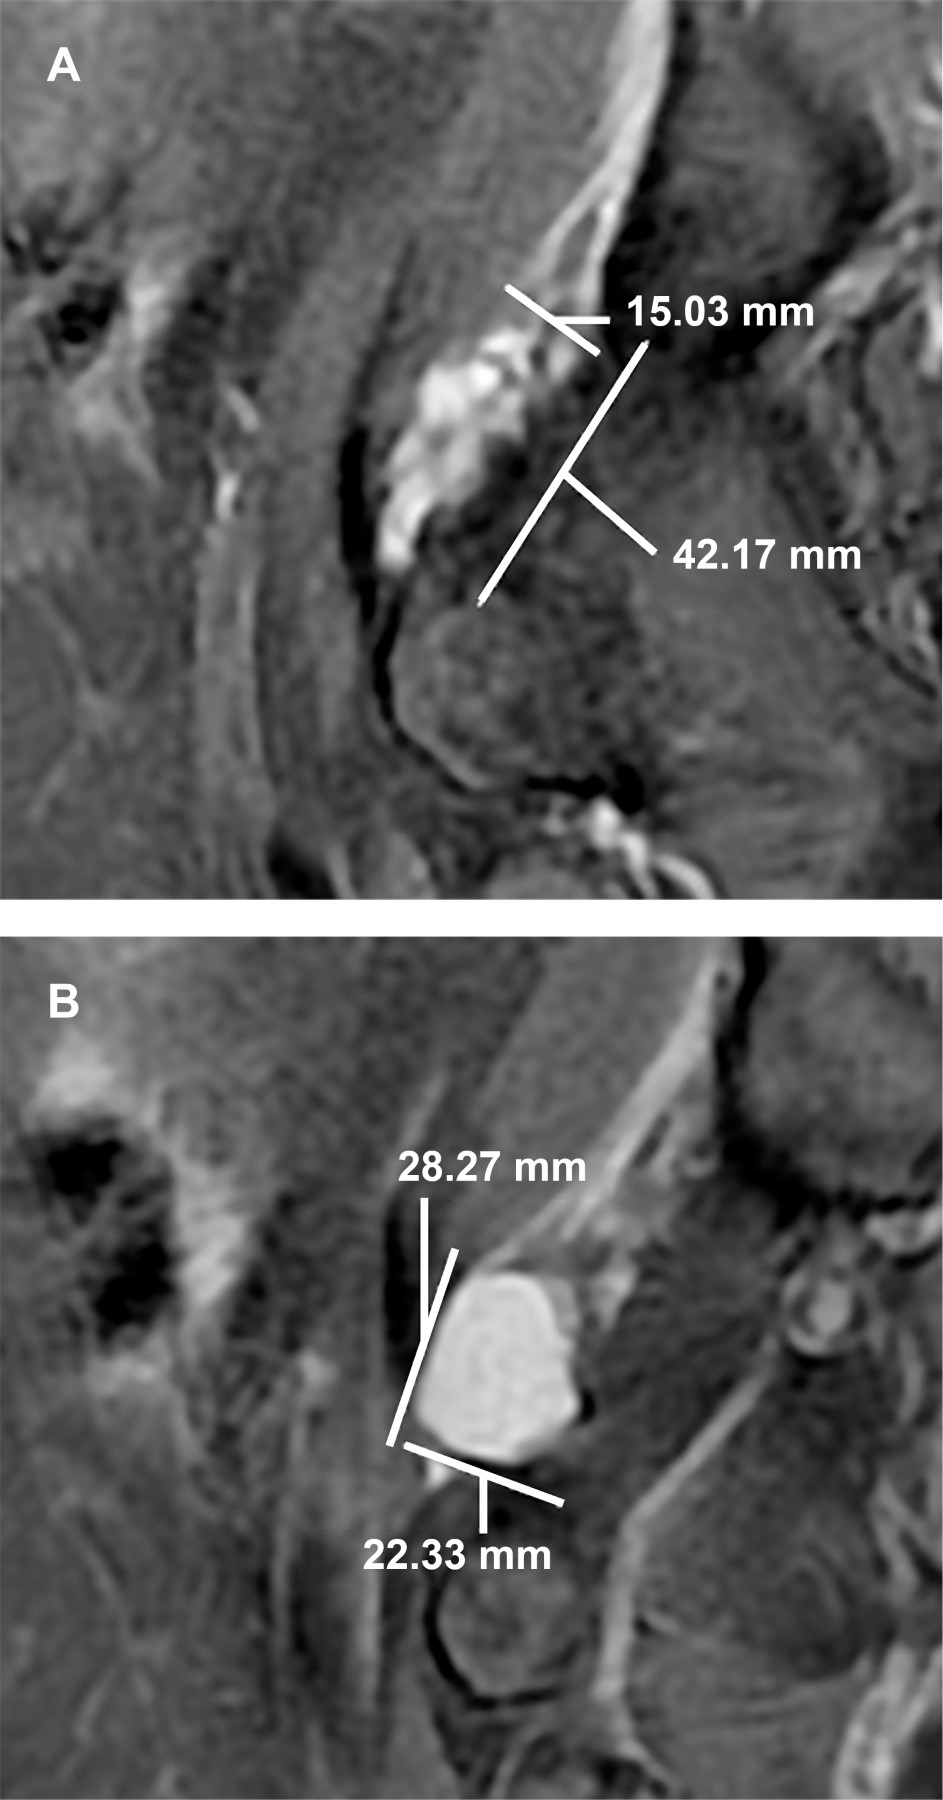

Se le realizó estudio de resonancia magnética de cadera derecha en secuencias potenciadas en T1, T2 y saturación grasa en los planos coronal, sagital y axial. Se observó fractura del labrum acetabular derecho con imagen sacular, de aspecto pediculado multilobulado, de contenido líquido, mide en el plano sagital de 42 × 15 mm, así como imagen circular bien delimitada que continúa hacia la porción superior y por debajo del músculo psoas, con diámetros en el plano sagital de 28 × 22 mm (Figura 1), en el plano coronal mide 32 × 27 cm (Figura 2) y en el axial 32 × 23 mm (Figura 3), sugestiva de quiste paralabral. Signos discretos de coxartrosis bilateral e hipotrofia de los músculos de la región glútea del lado derecho en comparación con el lado izquierdo.

Figura 1